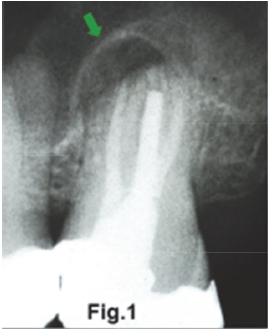

An elderly female patient presented with the main complaint that she had not slept on occasions over the past three weeks due to a severe throbbing pain on the right side of her face. She reported experiencing the same pain when bending down or drinking hot coffee. Figure 1 is an intra-oral radiograph of the third molar of the patient. What important radiological findings are discernible and what are your differential diagnoses?

The intra-oral radiograph (Fig.1) shows a lesion at the apex of the 18. The lesion has extended to destroy a portion of the antral floor. There is also loss of the lamina dura and the presence of a "halo" (green arrow) of periosteal new bone suggestive of an osteitis. Some authors refer to this lesion as a localized mucositis or sinusitis of the left maxillary sinus. A Water's view of another patient (Fig. 2) shows an opaque right maxillary sinus and a classic air-fluid level (red arrow) in the left sinus, features which are consistent with acute sinusitis. Another example of acute sinusitis is discernible on the axial CT (Fig. 3) scan of another patient showing a clearly opacified left maxillary sinus with mucosal thickening and an air-fluid level (red arrow). Acute sinusitis presents clinically with facial pain, headaches, local tenderness and purulent discharge and is a common infection of the maxillary sinuses. Figure 4 is a Water's view of the maxillary sinuses showing a very sclerotic right sinus and small sclerotic maxillary antra in the left sinus (purple arrows), which is suggestive of chronic sinusitis. An axial CT scan (Fig. 5) of the same patient shows marked thickening of the walls of the right maxillary sinus with a thickened mucosa. The medial wall defects indicate that prior nasal antrostomies had been performed (blue arrow).